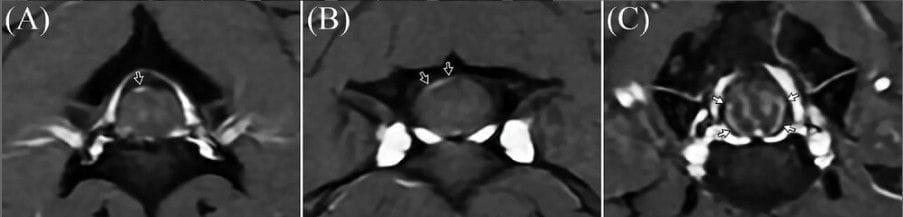

Categorization of the location and the shape of cervical spinal meningeal enhancement on fat-saturated images. The location of meningeal enhancement was classified as dorsal, lateral, or ventral of the meninges. The shape was categorized as long segments, short segments, or spots by comparing the length of the enhanced area to the maximal spinal cord diameter. An enhanced region was defined as a long segment if its length exceeded 50% of the maximal spinal cord diameter, as a short segment if its length ranged between 25% and 50% of the maximal spinal cord diameter, and as a spot if it was shorter than 25% of the maximal spinal cord diameter. For example, according to these criteria, the images were classified as spot enhancement of the dorsal meninges (A, open arrow), short segment enhancement of the dorsal meninges (B, open arrows), and long segment enhancement of the lateral and ventral meninges (C, closed arrows). Slice thickness = 2 mm, spacing = 0.2 mm, FOV = 140 × 140 mm; T1CEFS imaging parameters: TR = 481 ms, TE = 10 ms, NEX = 2, flip angle = 111°.